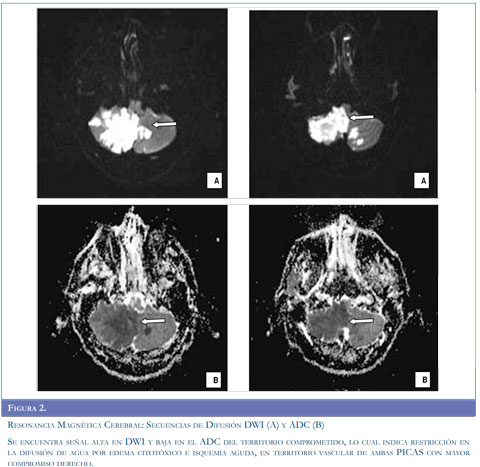

Con los argumentos descritos se realizó estudio de resonancia magnética del cerebro (Figuras 1 y 2) que evidenció infarto isquémico agudo del territorio de la arteria cerebelosa posteroinferior derecha (PICA), ecografía Doppler de vasos del cuello (Figura 3) que muestró aumento de las resistencias de las curvas obtenidas en la arteria vertebral derecha, con disminución significativa de su velocidad picosis-tólica y curvas con aspecto preoclusivo por lo cual se sospechó disección de la arteria vertebral. Se realizó panangiografía cerebral (Figura 4) que concluyó en disección de la arteria vertebral derecha con oclusión distal permitiendo aceptar la hipótesis planteada.